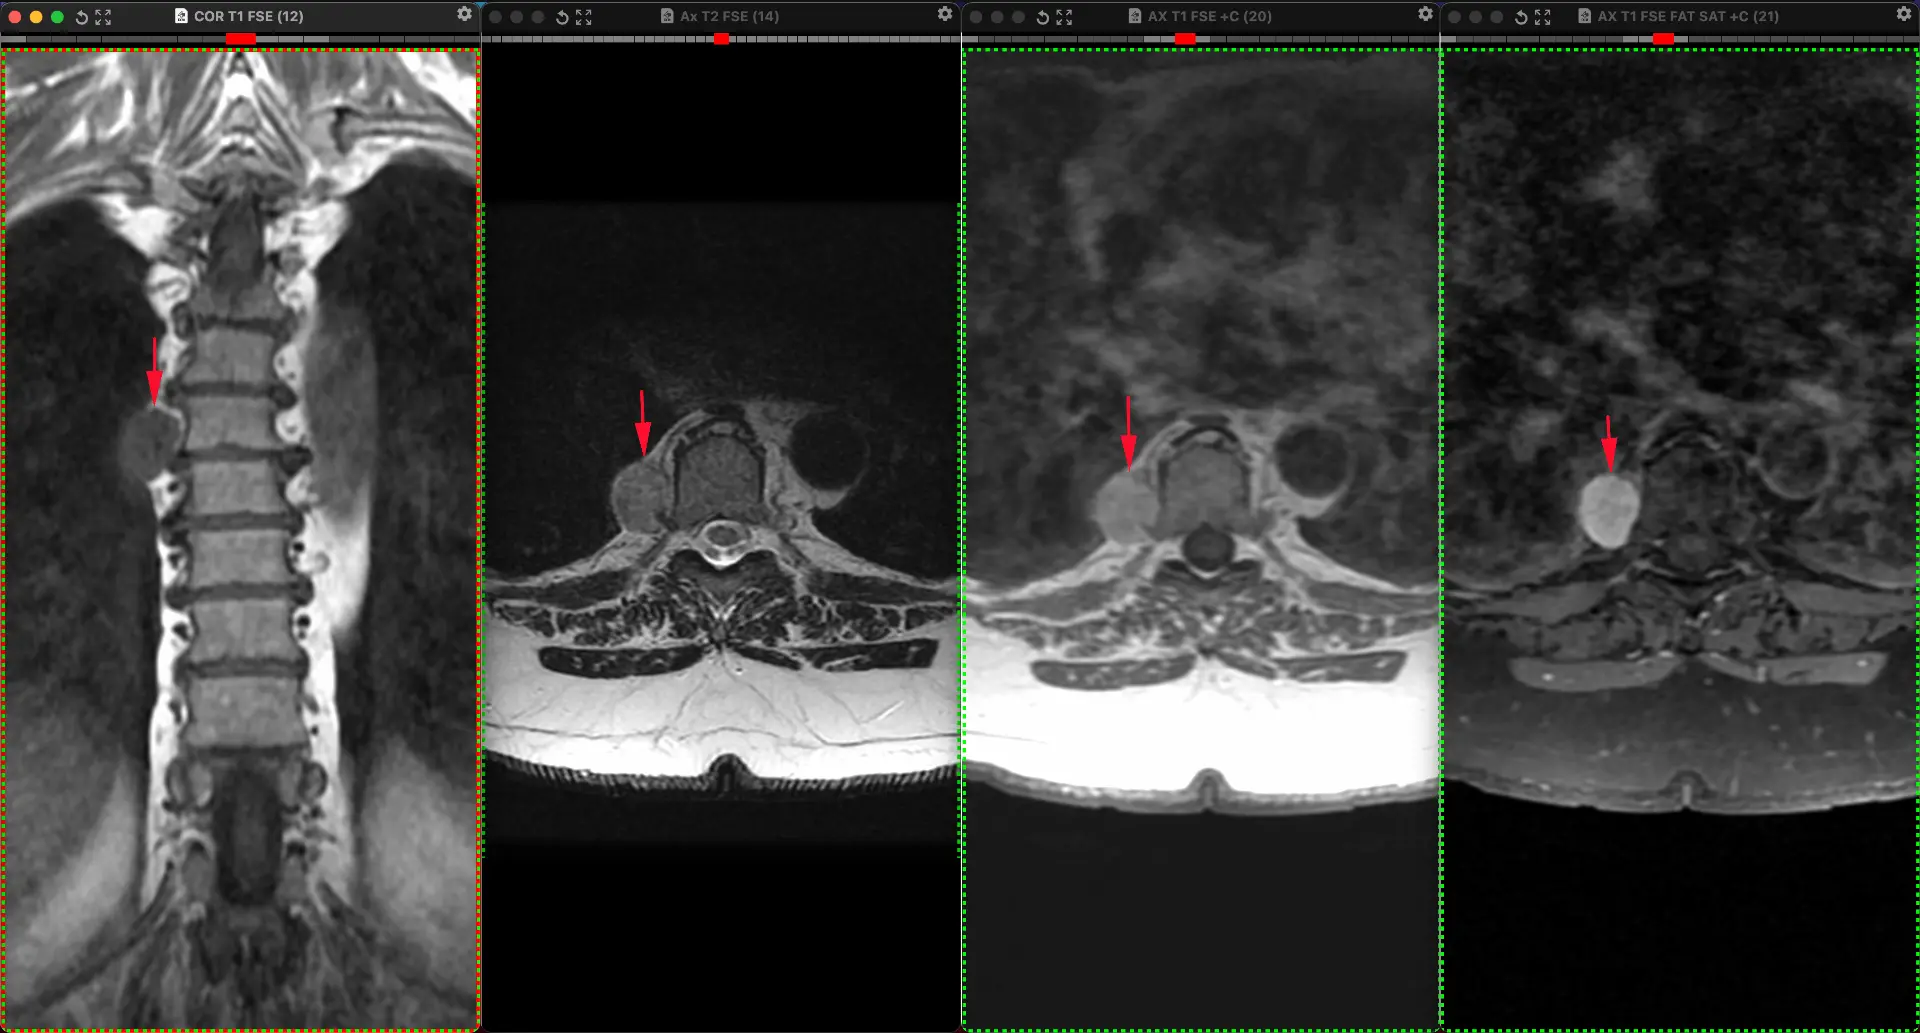

И ещё одна предполагаемая шваннома заднего средостения у женщины, на сей раз 38 лет, обследованной не по её поводу. Бессимптомная, как и почти всегда.

👍 45

Небезосновательно предполагаемая шваннома заднего средостение у женщины 54 лет, обследованной не по её поводу. Бессимптомная, как и почти всегда.

Опухоли нервной системы чаще всего встречаются среди первичных новообразований средостения. Львиная доля их — доброкачественные. Шванномы — самые частые нейрогенный опухоли в грудной клетке, которые развиваются из шванновских клеток периферических нервов (причём, любых, вплоть до самых мелких и необязательно спинномозговых) и часто сидят в заднем средостении. Обнаруживаются почти всегда случайно при проведении различных методов визуализации.

Интраторакальная шваннома чаще всего расположена в заднем средостении. Это - медленно растущая доброкачественная опухоль с низкой вероятностью стать злокачественной. В крайне редких случаях злокачественной трансформации могут встречаться плеоморфные веретенообразные клетки и некротические и геморрагические изменения. Как и в данном случае, опухоль обнаруживается случайно при визуализации: эхокардиография, гастроэндоскопия, КТ или МРТ. Симптомы в подавляющем большинстве случаев, отсутствуют, но могут появиться, если опухоль начнет давить на окружающие органы.